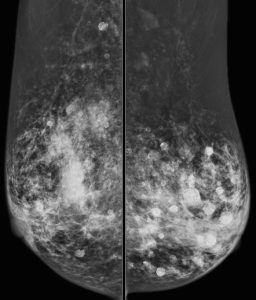

A 60-year-old woman presents for a screening mammogram:

What is responsible for the appearance of this mammogram?

C. History of direct silicone injections

Explanation: Direct injection of silicone is a method of breast augmentation that is illegal in the United States, but may still be practiced in other countries. The practice results in a mammogram with multiple high density masses (with rim calcifications) and areas of greatly increased density. Extremely dense lymph nodes may also be present. These high-density silicone breast masses make it difficult to detect a breast cancer on both physical exam and mammography.

Steatocystoma multiplex is a skin disorder, manifesting in the breast as multiple bilateral subcutaneous oil cysts. Although this patient has multiple rim calcifications (which can also occur with oil cysts), steatocystoma multiplex would not explain the presence of so many areas of greatly increased density.